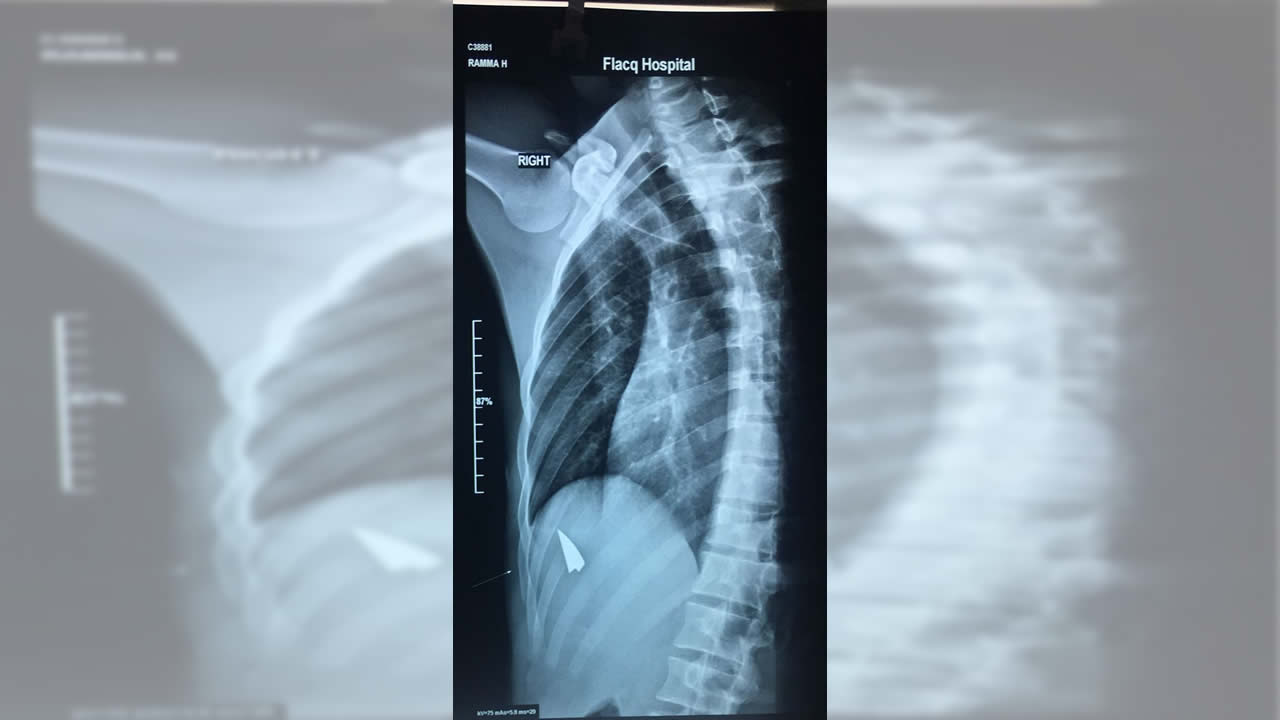

L’élève de Upper 6 a été transporté à l’hôpital. Vu son état, il a été admis. L’enquête de la police est menée parallèlement avec celle du ministère de l’Éducation. Il nous revient que les deux élèves appartiennent à des groupes différents au sein de l’établissement qui ont l’habitude de s’affronter.